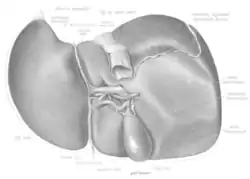

The liver is a dark reddish brown, wedge-shaped organ with two lobes of unequal size and shape. A human liver normally weighs approximately 1.5 kilograms (3.3 pounds)[9] and has a width of about 15 centimetres (6 inches).[10] There is considerable size variation between individuals, with the standard reference range for men being 970–1,860 grams (2.14–4.10 lb)[11] and for women 600–1,770 g (1.32–3.90 lb).[12] It is both the heaviest internal organ and the largest gland in the human body. It is located in the right upper quadrant of the abdominal cavity, resting just below the diaphragm, to the right of the stomach, and overlying the gallbladder.[5]

Lobes

The liver is grossly divided into two parts when viewed from above – a right and a left lobe – and four parts when viewed from below (left, right, caudate, and quadrate lobes).[14]

The falciform ligament makes a superficial division of the liver into a left and right lobe. From below, the two additional lobes are located between the right and left lobes, one in front of the other. A line can be imagined running from the left of the vena cava and all the way forward to divide the liver and gallbladder into two halves.[15] This line is called Cantlie's line.[16]

Other anatomical landmarks include the ligamentum venosum and the round ligament of the liver, which further divide the left side of the liver in two sections. An important anatomical landmark, the porta hepatis, divides this left portion into four segments, which can be numbered starting at the caudate lobe as I in an anticlockwise manner. From this parietal view, seven segments can be seen, because the eighth segment is only visible in the visceral view.[17]